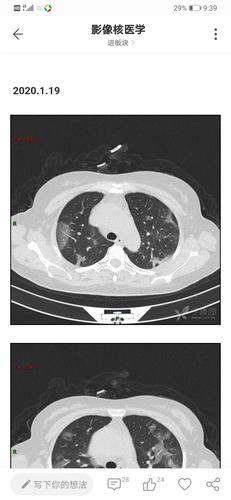

新冠肺炎肺部影像

新冠肺炎肺部影像,新冠肺炎

新冠肺炎的影像学表现小结

因为大众已了解到,新冠病毒感染后肺部ct会出现斑片状磨玻璃影

新冠肺炎(来自丁香园))

其它 阅图识病之新冠肺炎一例 写美篇 影像所示: 双肺可见多发大小不